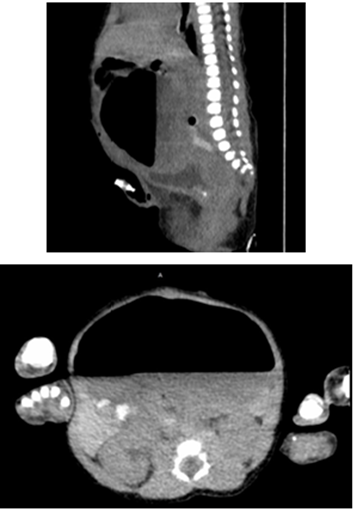

Se realizaron estudios complementarios, entre ellos radiografía de abdomen simple y tomografía axial computarizada de abdomen y pelvis para confirmar el diagnóstico prenatal, donde se evidenció dilatación de asas intestinales en hemiabdomen superior y ausencia de patrón aéreo (Figura 5 - 6). Fue valorado por cirugía pediátrica, quien en vista de los hallazgos decidió llevar a mesa operatoria realizándose laparotomía exploradora. Entre los hallazgos, se describió dilatación intestinal que abarcaba desde el yeyuno hasta parte del íleon distal, de aproximadamente 40 cm, que compartía el mismo mesenterio con el intestino delgado duplicado, lo cual llevó a obstrucción intestinal; el resto del intestino desfuncionalizado, por lo que se corroboró el diagnóstico de duplicación intestinal; además se encontraron bandas de Ladd, las cuales son bandas fibrosas que se asocian a malrotación intestinal y producen obstrucción intestinal a nivel del duodeno (Figura 7).

Figura 6 Tomografía axial computarizada de abdomen y pelvis, en corte sagital y axial sin administración de contraste endovenoso, con contraste oral, se evidencia dilatación que se extiende desde cardias, hasta íleon, con evidencia de nivel hidroaéreo sugestivo de obstrucción intestinal.